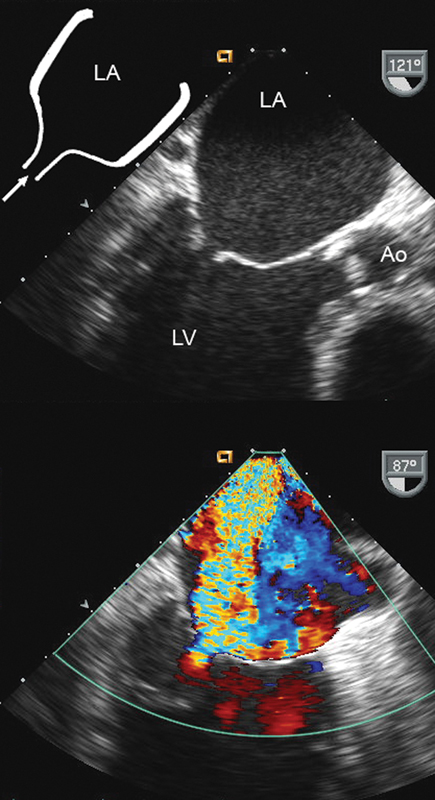

فحوصات تشخيصية لبعض امراض القلب والشرايين التاجية